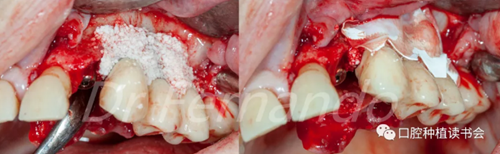

在無菌容器中將Cerasorb ?M(科盧森)骨粉與哌拉西林-他唑巴坦透明質(zhì)酸鈉溶液混合,將骨粉放置在缺損處,并用預(yù)先浸泡過哌拉西林-他唑巴坦透明質(zhì)酸鈉溶液的膠原膜覆蓋該區(qū)域并進(jìn)行縫和(圖15、圖16 )。

圖15 種植體周圍骨缺損區(qū)植骨+覆蓋可吸收膜

圖16 嚴(yán)密關(guān)閉創(chuàng)口